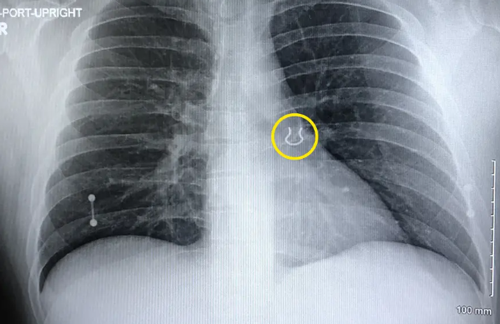

聽起來更像是意外「窒息」,但還有更窒息的,有個(gè)老哥鼻環(huán)丟了,他找了五年,最后在自己的肺里找到了。

這個(gè)老哥名叫Joey Lykins,有一天他睡醒后發(fā)現(xiàn)有點(diǎn)不對勁,那就是鼻環(huán)不見了。

而這個(gè)老哥是心大,找不到就不找了,換了鼻環(huán)繼續(xù)生活。但隨著時(shí)間的推移,他開始不斷咳嗽,肺部逐漸上演起了指環(huán)王的大戲,而這也快要了他的老命。

被折騰不輕的他不得不去醫(yī)院檢查,在順利手術(shù)后,五年前丟失的東西總算失而復(fù)得了。